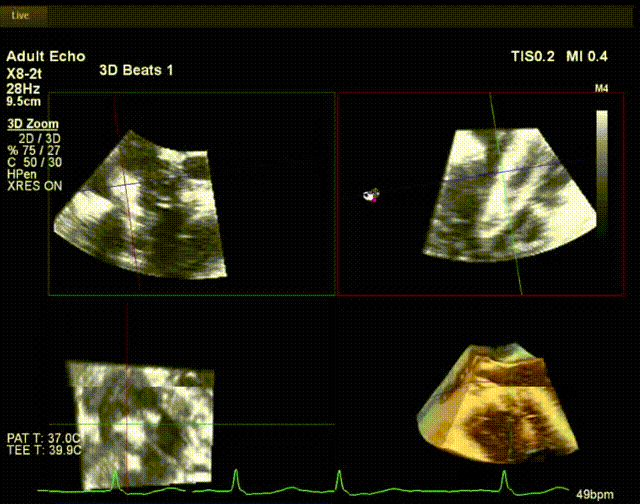

術中超聲

手術在全麻狀態下開展,此次手術采用經頸靜脈入路的方式。在TEE及DSA雙重引導下,術者調整輸送器頭端角度使得其與三尖瓣瓣環平面垂直。在輸送器進入右心室后釋放室間隔錨定裝置,而后釋放瓣葉夾持件(2個耳片結構)成垂直狀態。在TEE及DSA確定夾持件固定至三尖瓣葉根部且位于右室側后釋放人工瓣心房側盤片。隨后調整瓣膜同軸性以及室間隔錨定件位置(貼合室間隔),進而釋放室間隔錨定裝置,并再次確認瓣膜位置、穩定性及同軸性,解離人工瓣膜與輸送器間連接,并撤出輸送器,完成了LuX-Valve Plus人工三尖瓣瓣膜的植入。